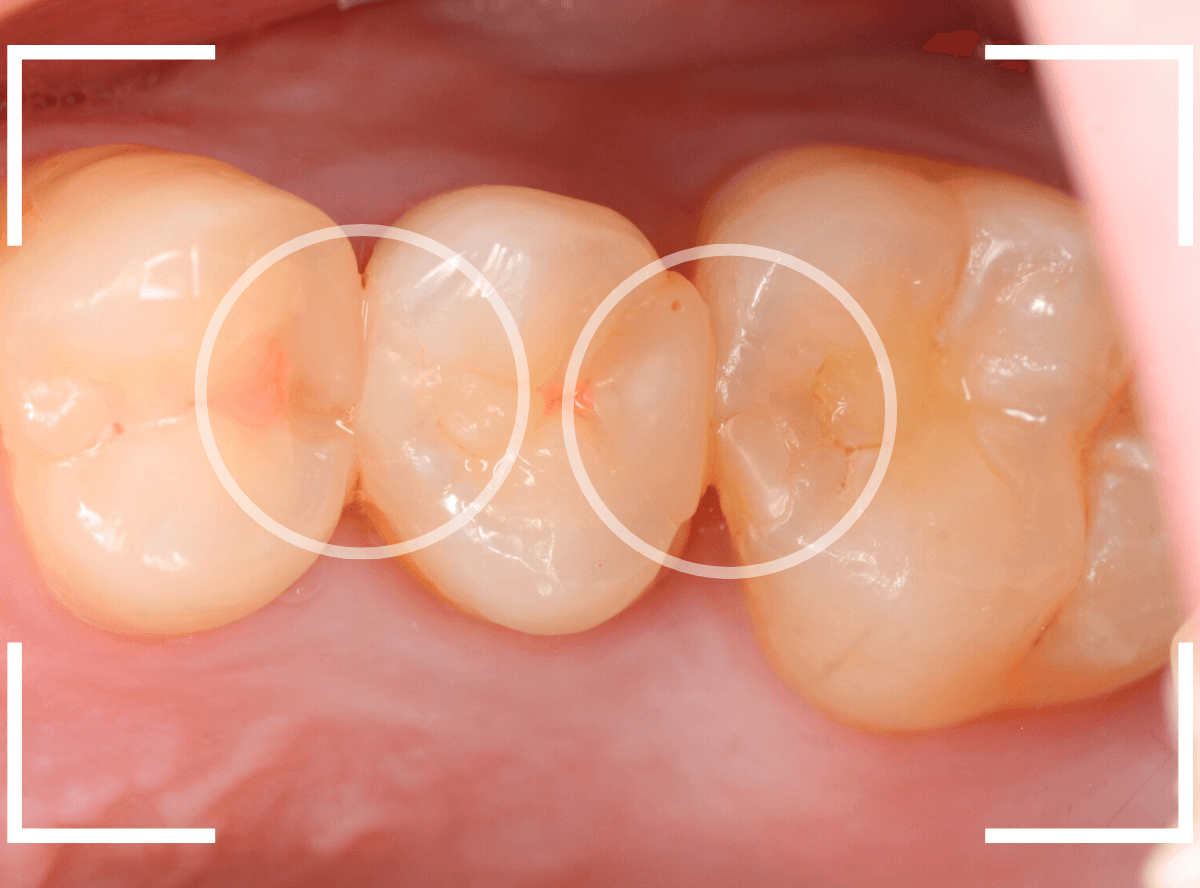

Case.9 レジンの中で大きく広がった虫歯

他の歯の治療希望で来院された患者さんです。

検査をすると、他の場所にも大きな虫歯が見つかりました。

レジン(つめもの)の下の虫歯で、この写真では、わかりづらいですが、中で広がっています。

このように一度治療した箇所は虫歯の再発しやすい部分でもあります。

特に隣の歯との間のレジンの中は虫歯が見つかる事が多いです。

自覚症状がなくても、定期的なメンテナンスとレントゲン写真での確認をおすすめします。